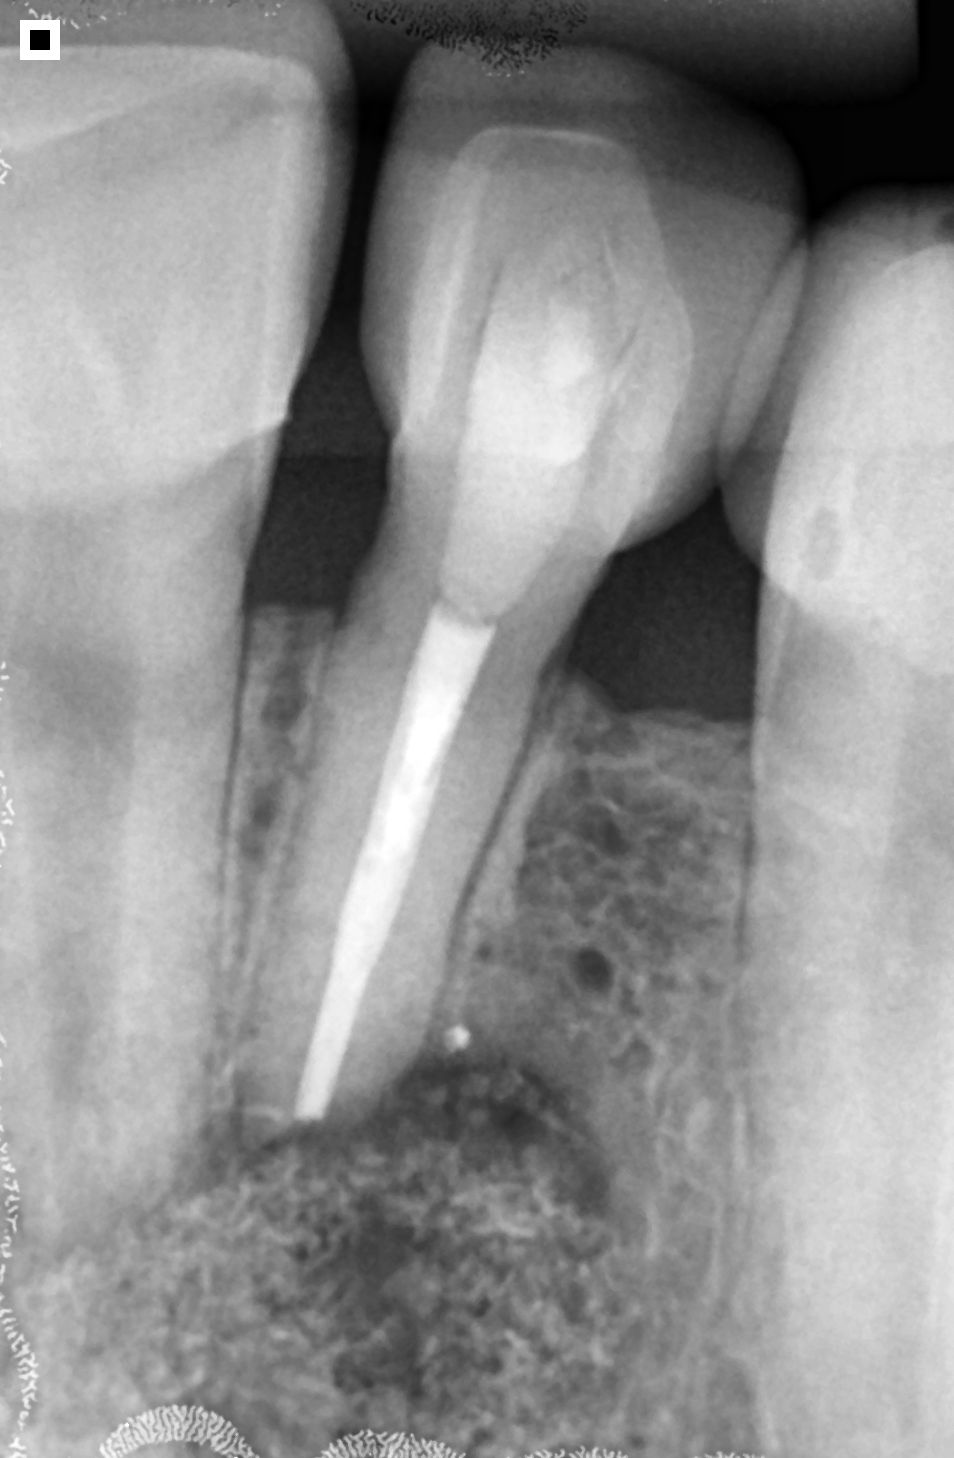

O diagnóstico da necessidade de uma apicectomia se baseia na avaliação clínica e nos exames de imagem. A radiografia e a tomografia computadorizada visualizam com precisão a extensão da lesão.

No caso citado, os exames mostraram claramente a presença de uma lesão no ápice do dente, tanto na região lateral quanto central da raiz, confirmando a necessidade de intervenção cirúrgica.